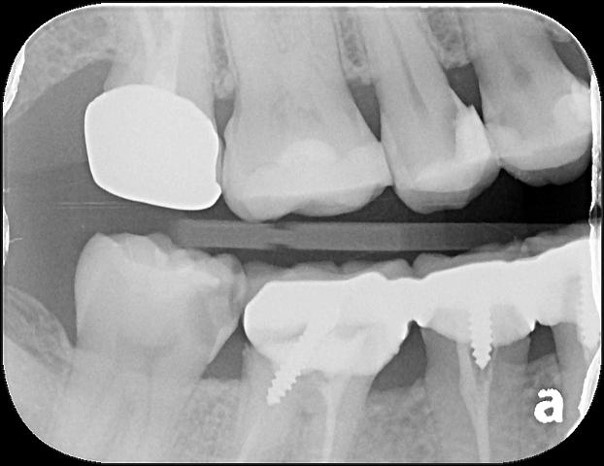

治療前,右下顎第二大臼齒二次蛀牙

右下顎第二大臼齒二次蛀牙